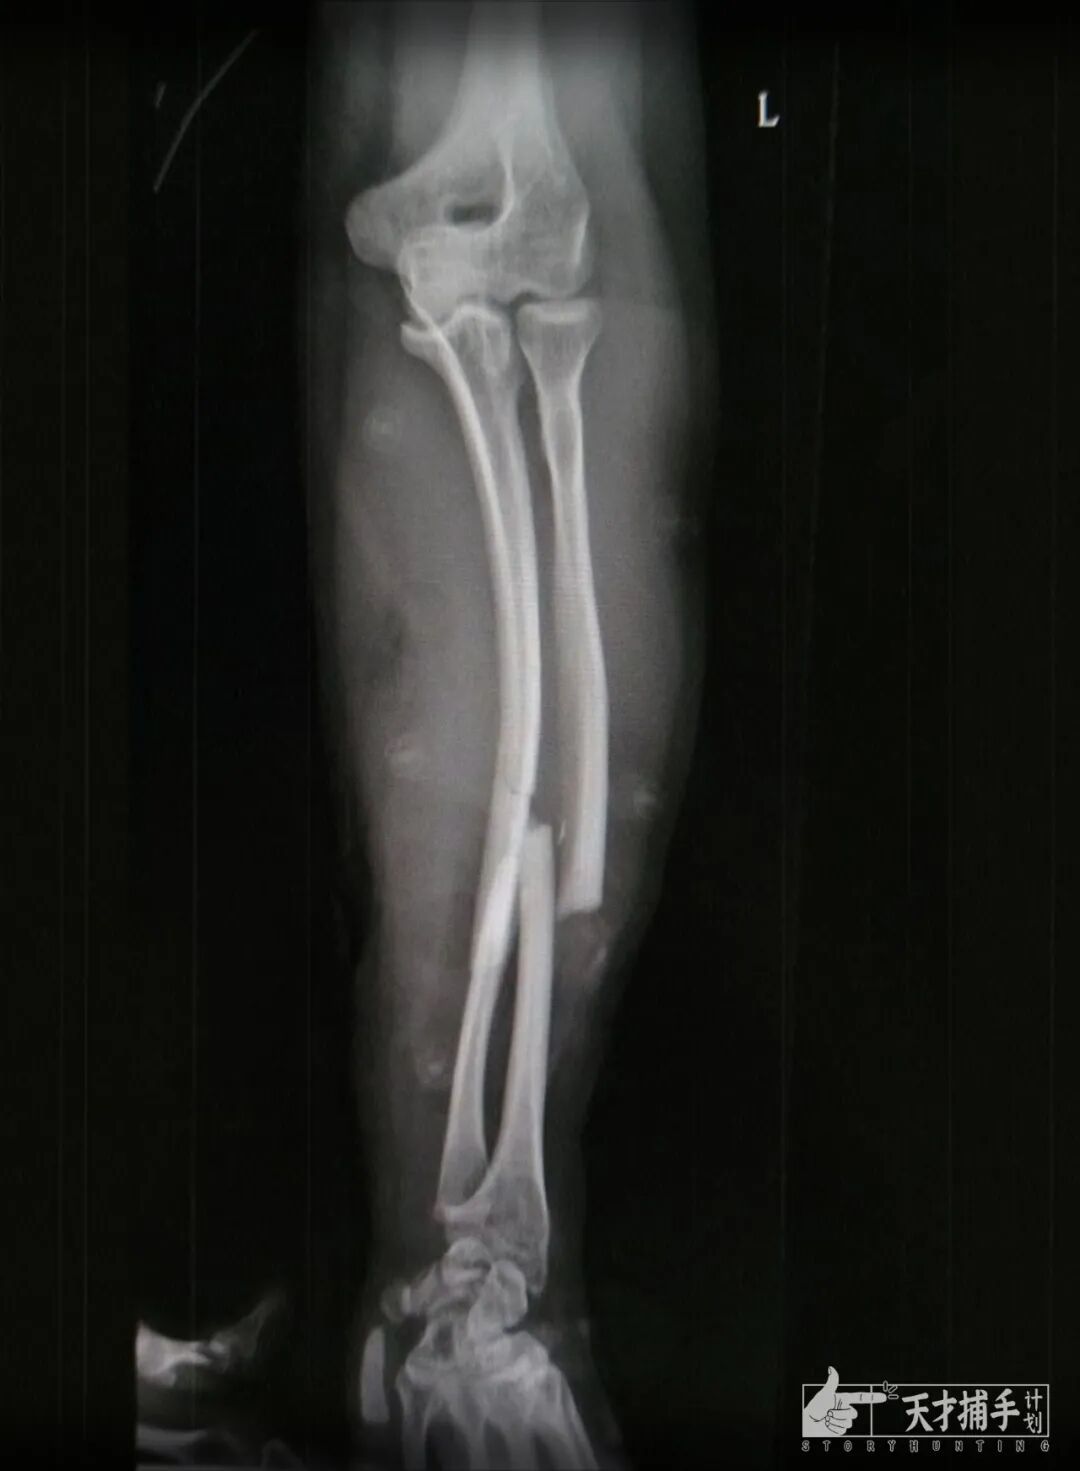

Image

这是最近一次手臂骨折的X光片